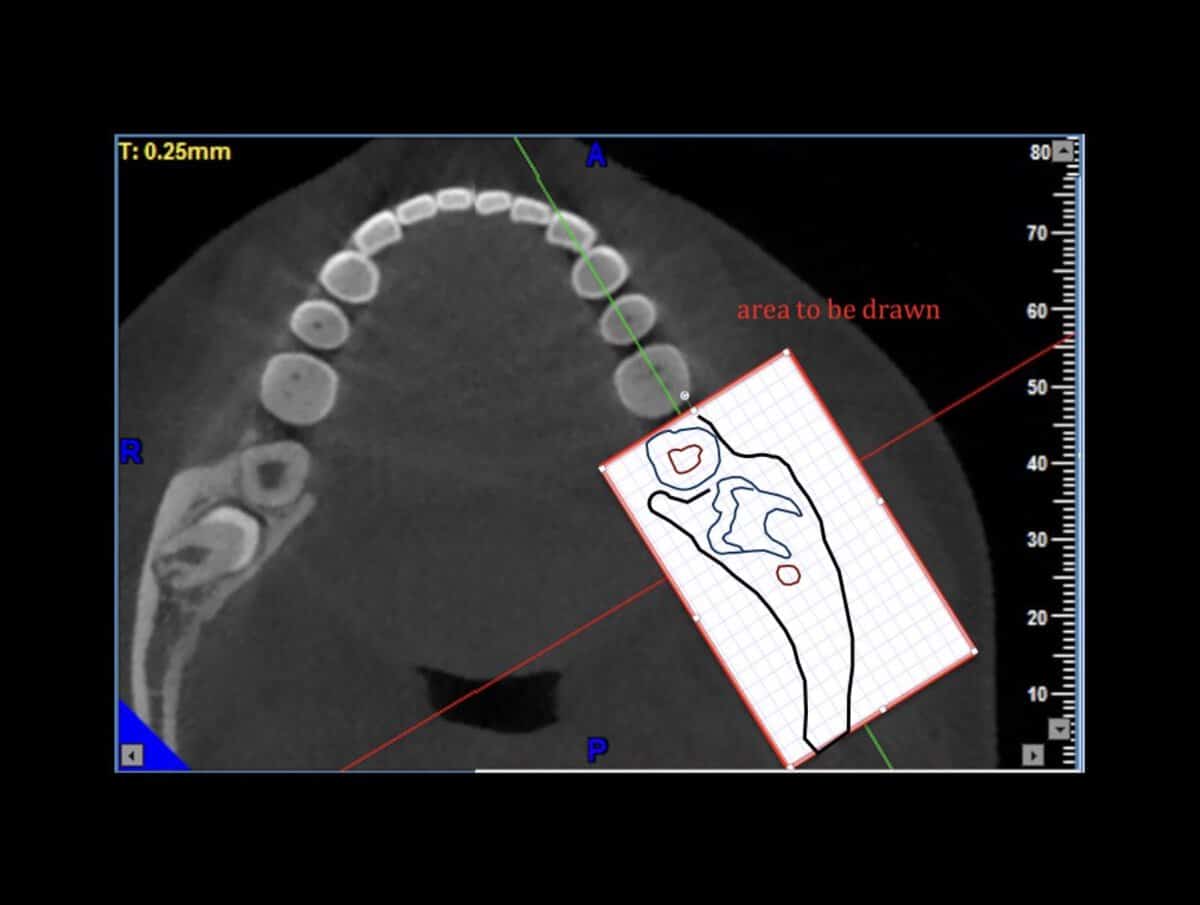

The DASRA Challenge, free online:

Study the anatomy

use detailed slices from CBCT data of a specific location

Synthesize

Combine different slices and views

Reconstruct

Find the configuration of the missing part from a list f available options

An important question for everyone. Do not mix SRA with other surgical skills such as cutting and suturing, SRA is an underlying skill. It will “naturally” grow with every surgery, but if you want to excel it you have to target it with specific training, just like anything else. And if you want to test your level, you also need some specific test. Many tests are available to test SRA, most of them are very generic though. Some time ago with Dr. James Chow and Dr. Coral Yao we developed a test specific to understanding surgical anatomy with the use of CBCT. The challenge here is to reconstruct a 3Dimensional anatomic space from 3 2D representations, as we routinely have to do while “reading” a CBCT. The test was called DASRA and was scientifically validated. It will give you an idea of the level of an important skill for implant surgery and it’s available online for free. Take the DASRA challenge and remember to leave us your thoughts and comments.